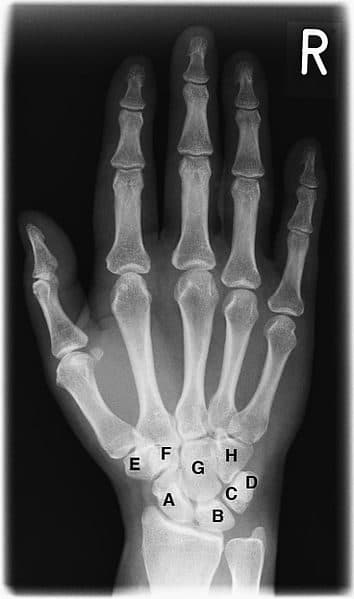

A complex of twenty-seven bones and intricate tendons enabling fine motor control. Compressive neuropathies and tenosynovitis lead the presentation list.